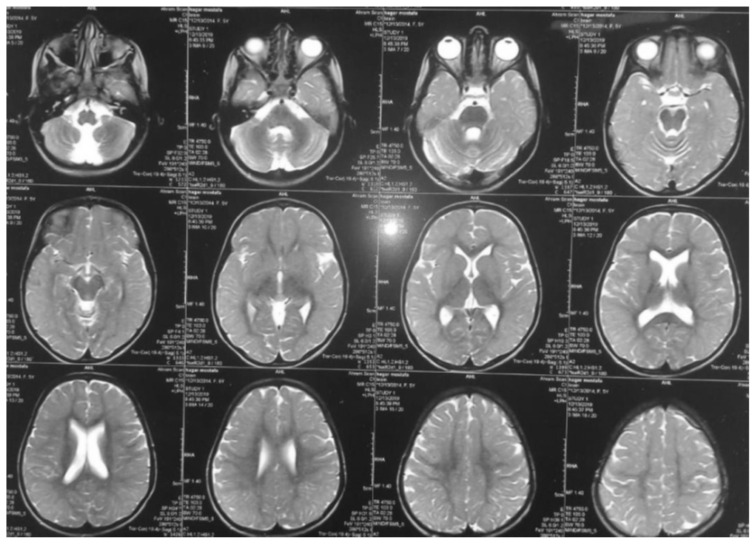

叶酸受体 1 基因(FOLR1)突变导致的脑叶酸转运缺陷,是由于叶酸通过血液:脉络膜:脑脊液(CSF)屏障的转运功能受损所致。这导致脑脊液中活性叶酸代谢物 5-甲基四氢叶酸含量偏低。我们报告了两名患有这种可治疗的脑叶酸转运缺乏症的儿童。八岁零九个月大的女婴发育迟缓,随后出现退步、癫痫发作和意向性震颤。经检查,患儿有小头畸形、全身肌张力低下、反射亢进、步态不稳和不协调等症状。脑部磁共振成像(MRI)显示脑室系统扩张和小脑萎缩。脑部计算机断层扫描(CT)显示脑部钙化。最后进行了全外显子测序,发现FOLR1基因第3外显子c.C382T p.R128W存在同型无义致病变异,确诊为脑叶酸缺乏症。12岁的女患儿自出生后就出现全面发育迟缓、肌阵挛性抽搐和认知能力退化。患儿全身肌张力低下,反射亢进。她的协调能力明显受到影响,并伴有意向性震颤和步态不平衡。脑部 CT 显示双侧基底节和脑室周围钙化,并伴有脑萎缩病变。脑部核磁共振成像显示小脑叶突出,伴有轻度脑萎缩病变。基因检测显示,在 FOLR1 C.327_328 delinsAC, p.Cys109Ter 中发现了一个同卵致病变体。两名患者开始肌肉注射亚叶酸,癫痫发作频率有所下降。然而,由于开始治疗较晚,他们的癫痫发作并没有完全停止。总之,如果患儿出现全面发育迟缓、顽固性肌阵挛性癫痫、共济失调并伴有神经影像学提示的小脑萎缩和脑钙化,则应怀疑其脑叶酸转运缺乏症。如果诊断较晚且治疗启动延迟,则对补充亚叶酸的反应是部分的。

Cerebral folate transport deficiency due to folate receptor 1 gene (FOLR1) gene mutation results from impaired folate transport across the blood: choroidplexus: cerebrospinal fluid (CSF) barrier. This leads to low CSF 5-methyltetrahydrofolate, the active folate metabolite. We are reporting two children with this treatable cerebral folate transport deficiency. Eight years and 9-month-old female presented with delayed milestones followed by regression, seizures, and intention tremors. On examination child had microcephaly, generalized hypotonia, hyperreflexia, unsteady gait, and incoordination. Magnetic resonance imaging (MRI) of brain revealed dilated ventricular system and cerebellar atrophy. Computed tomography (CT) of brain showed brain calcifications. Whole exome sequencing was finally performed, revealing homozygous nonsense pathogenic variant in FOLR1 gene in exon 3 c.C382T p.R128W, confirming the diagnosis of cerebral folate deficiency. Twelve-year-old female child presented with global developmental delay since birth, myoclonic jerks and cognitive regression. Child had generalized hypotonia and hyperreflexia. Her coordination was markedly affected with intention tremors andunbalanced gait. CT brain showed bilateral basal ganglia and periventricular calcifications with brain atrophic changes. MRI brain showed a prominent cerebellar folia with mild brain atrophic changes. Genetic testing showed a homozygous pathogenic variant was identified in FOLR1 C.327_328 delinsAC, p.Cys109Ter. Both patients were started on intramuscular folinic acid injections with a decrease in seizure frequency. However, their seizures did not stop completely due to late initiation of therapy. In conclusion, cerebral folate transport deficiency should be suspected in every child with global developmental delay, intractable myoclonic epilepsy, ataxia with neuroimaging suggesting cerebellar atrophy and brain calcifications. Response to folinic acid supplementation is partial if diagnosed late and treatment initiation is delayed.